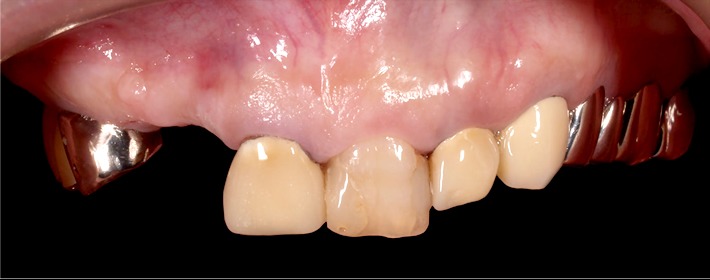

初診時

かつて抜歯してそのままにしていた箇所へのインプラント治療